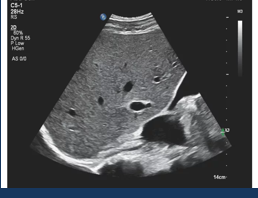

Difference b/w SHADOWING & ENHANCEMENT (nope)

(right image) enhancement = travels very well through fluid = benign

(left image) shadowing = sound beam tries to get through very dense → dense masses in breast likely cancerous